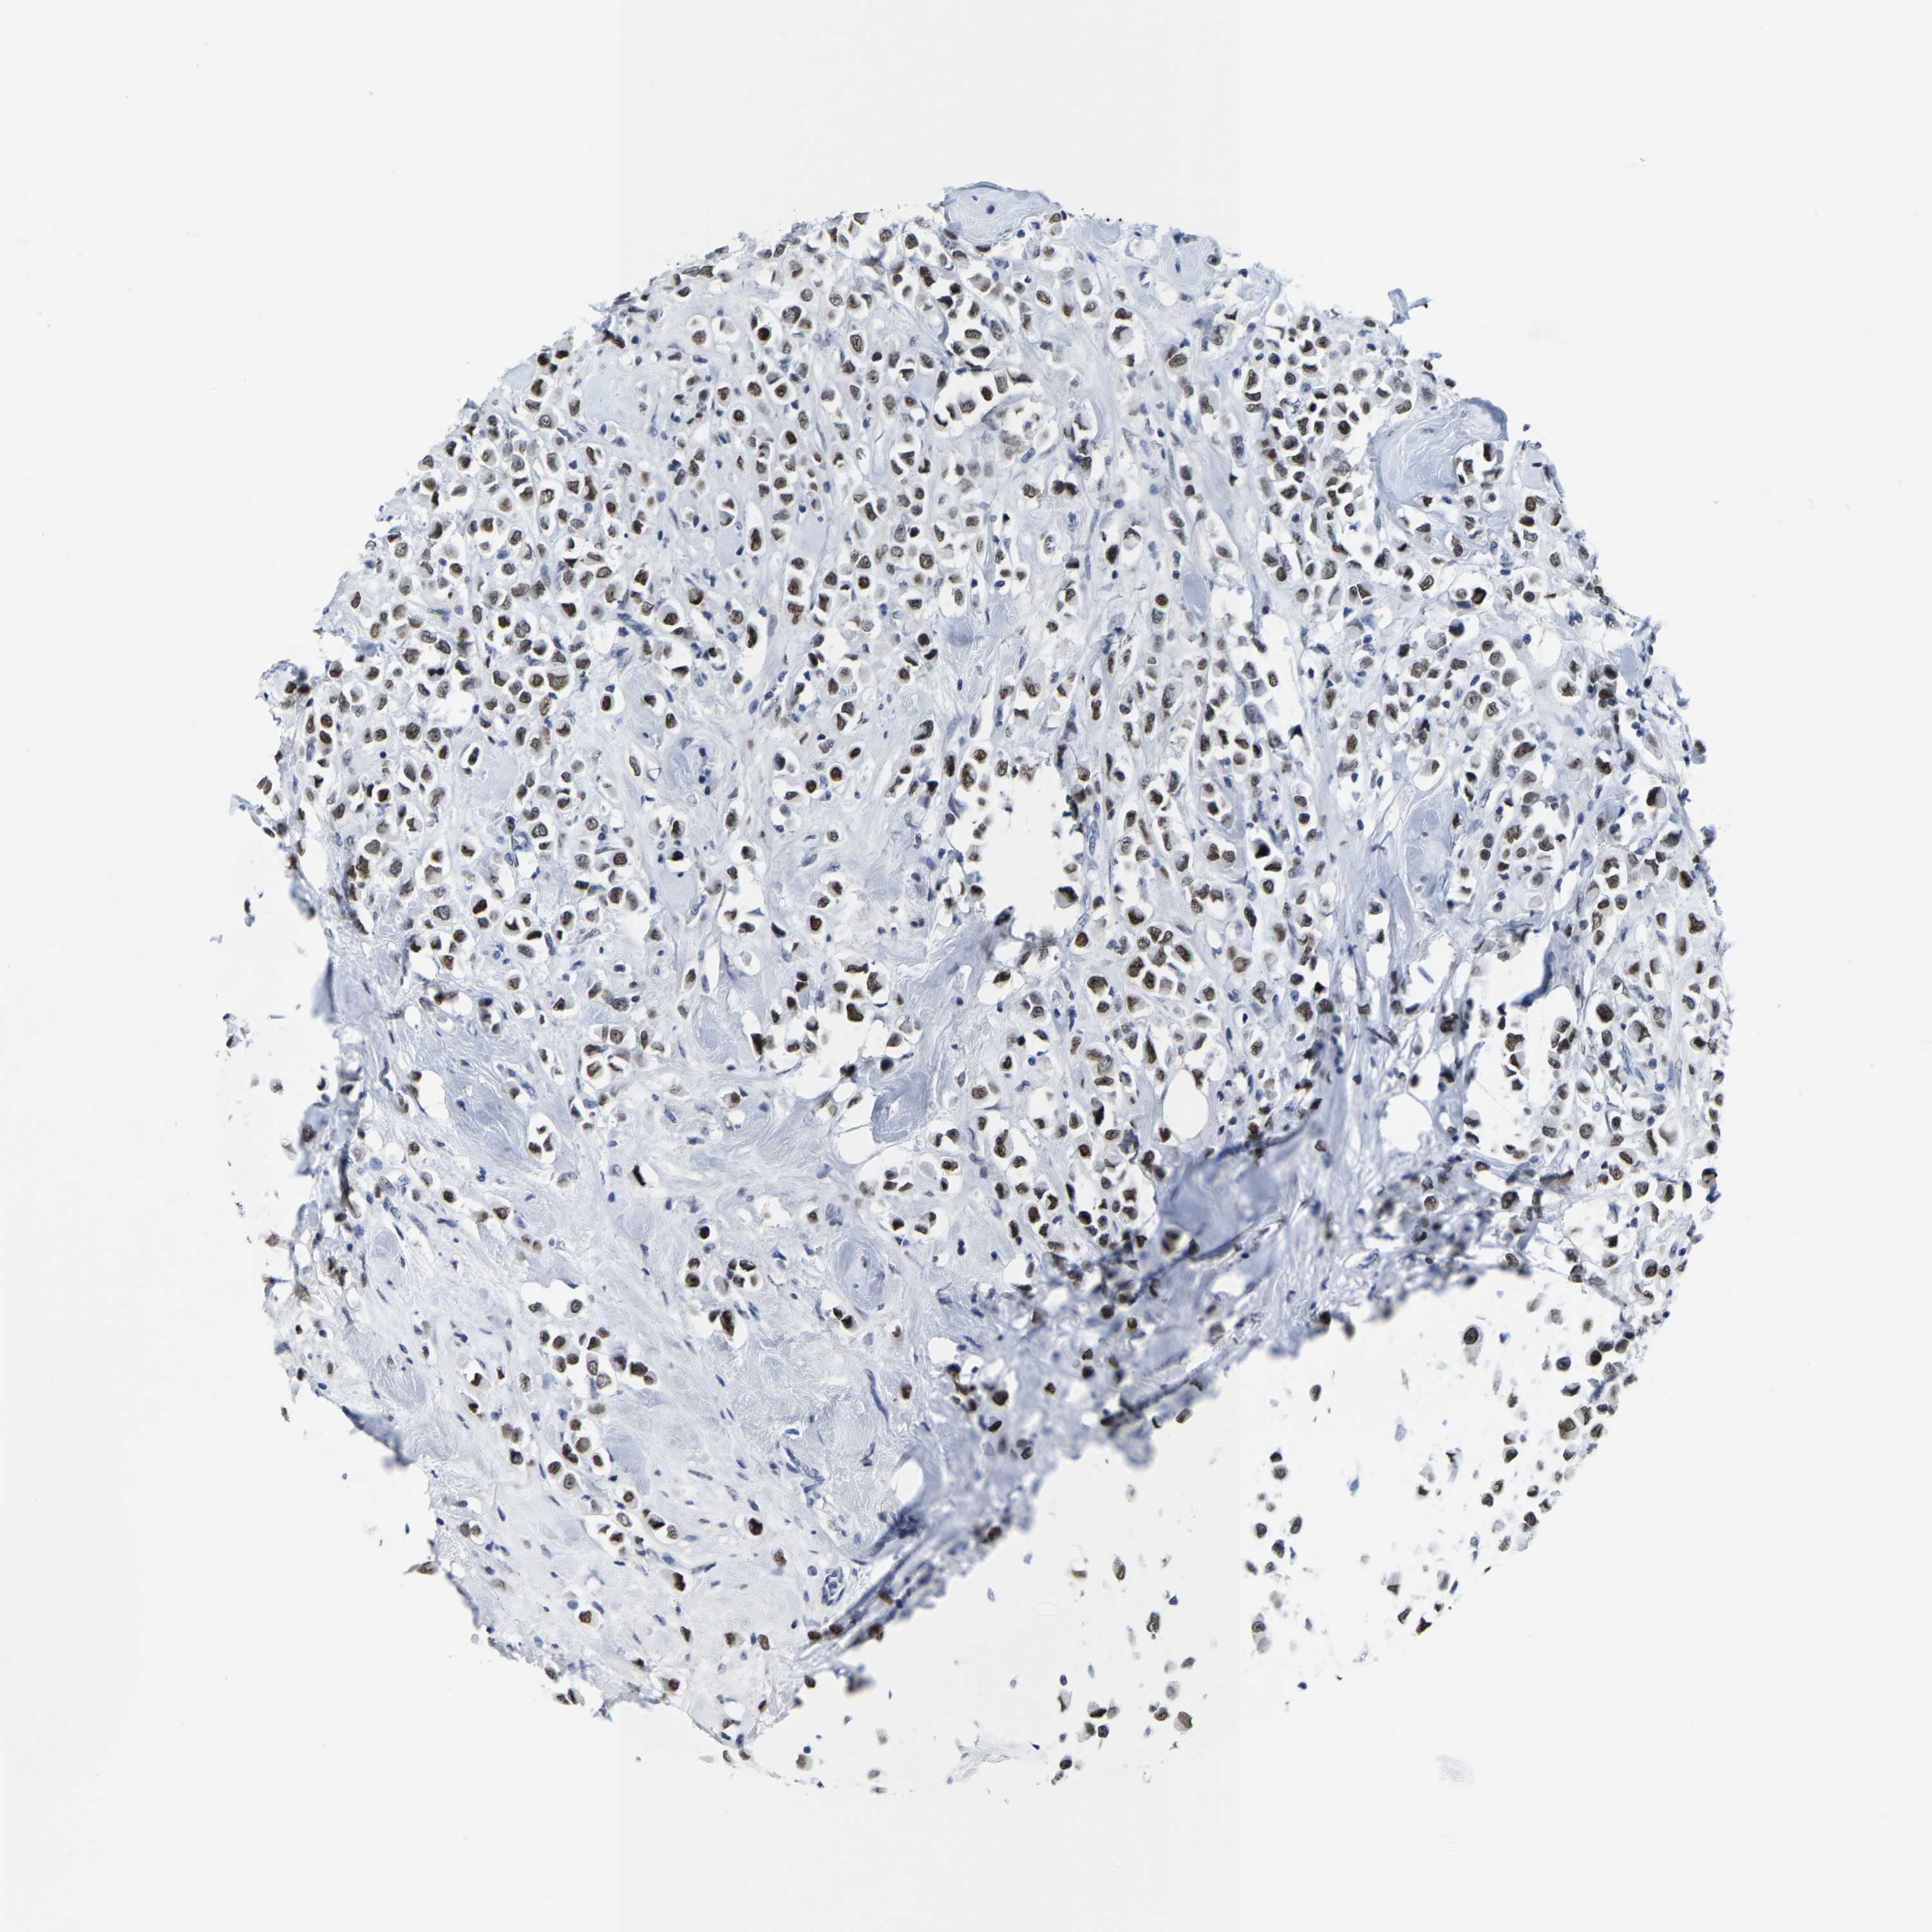

CANCER BREAST CANCER Show tissue menu

BRCA TCGA BRCA VALIDATION PROTEIN EXPRESSION